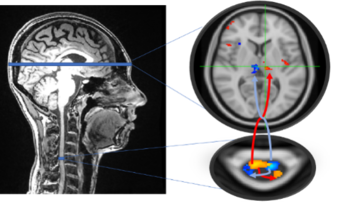

The Systems Neuroscience & Pain Laboratory at Stanford University (SNAPL) is actively recruiting a postdoctoral fellow who will join our research project on chronic pain. Funded by the National Institute of Health and directed by neuroscience professors Sean Mackey and Gary Glover, our goal is to investigate mechanisms of chronic pain using methods we developed to image the entire CNS via simultaneous spinal cord/brain fMRI.